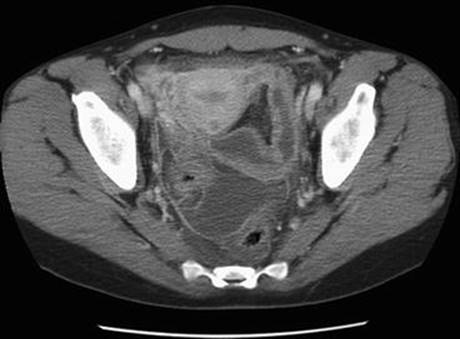

When the diagnosis of TOA is not clear following a pelvic ultrasound, a CT scan is recommended. CT scans can also detect gastrointestinal causes of pelvic abscess, such as diverticulitis or appendicitis, and bowel or gynecologic malignancy, which may also present as complex pelvic masses [19]. By CT scan, a TOA appears as a thick-walled, uniformly enhancing abscess, which may be multilocular [20]. The mesosalpinx and uterosacral ligaments may also appear thickened, and pyosalpinx is noted in 50 % of patients (Fig. 6.4).

Fig. 6.4

Computed tomographic image of pyosalpinx and tubo-ovarian abscess (Reprinted from Chappell and Wiesenfeld [19], with permission)